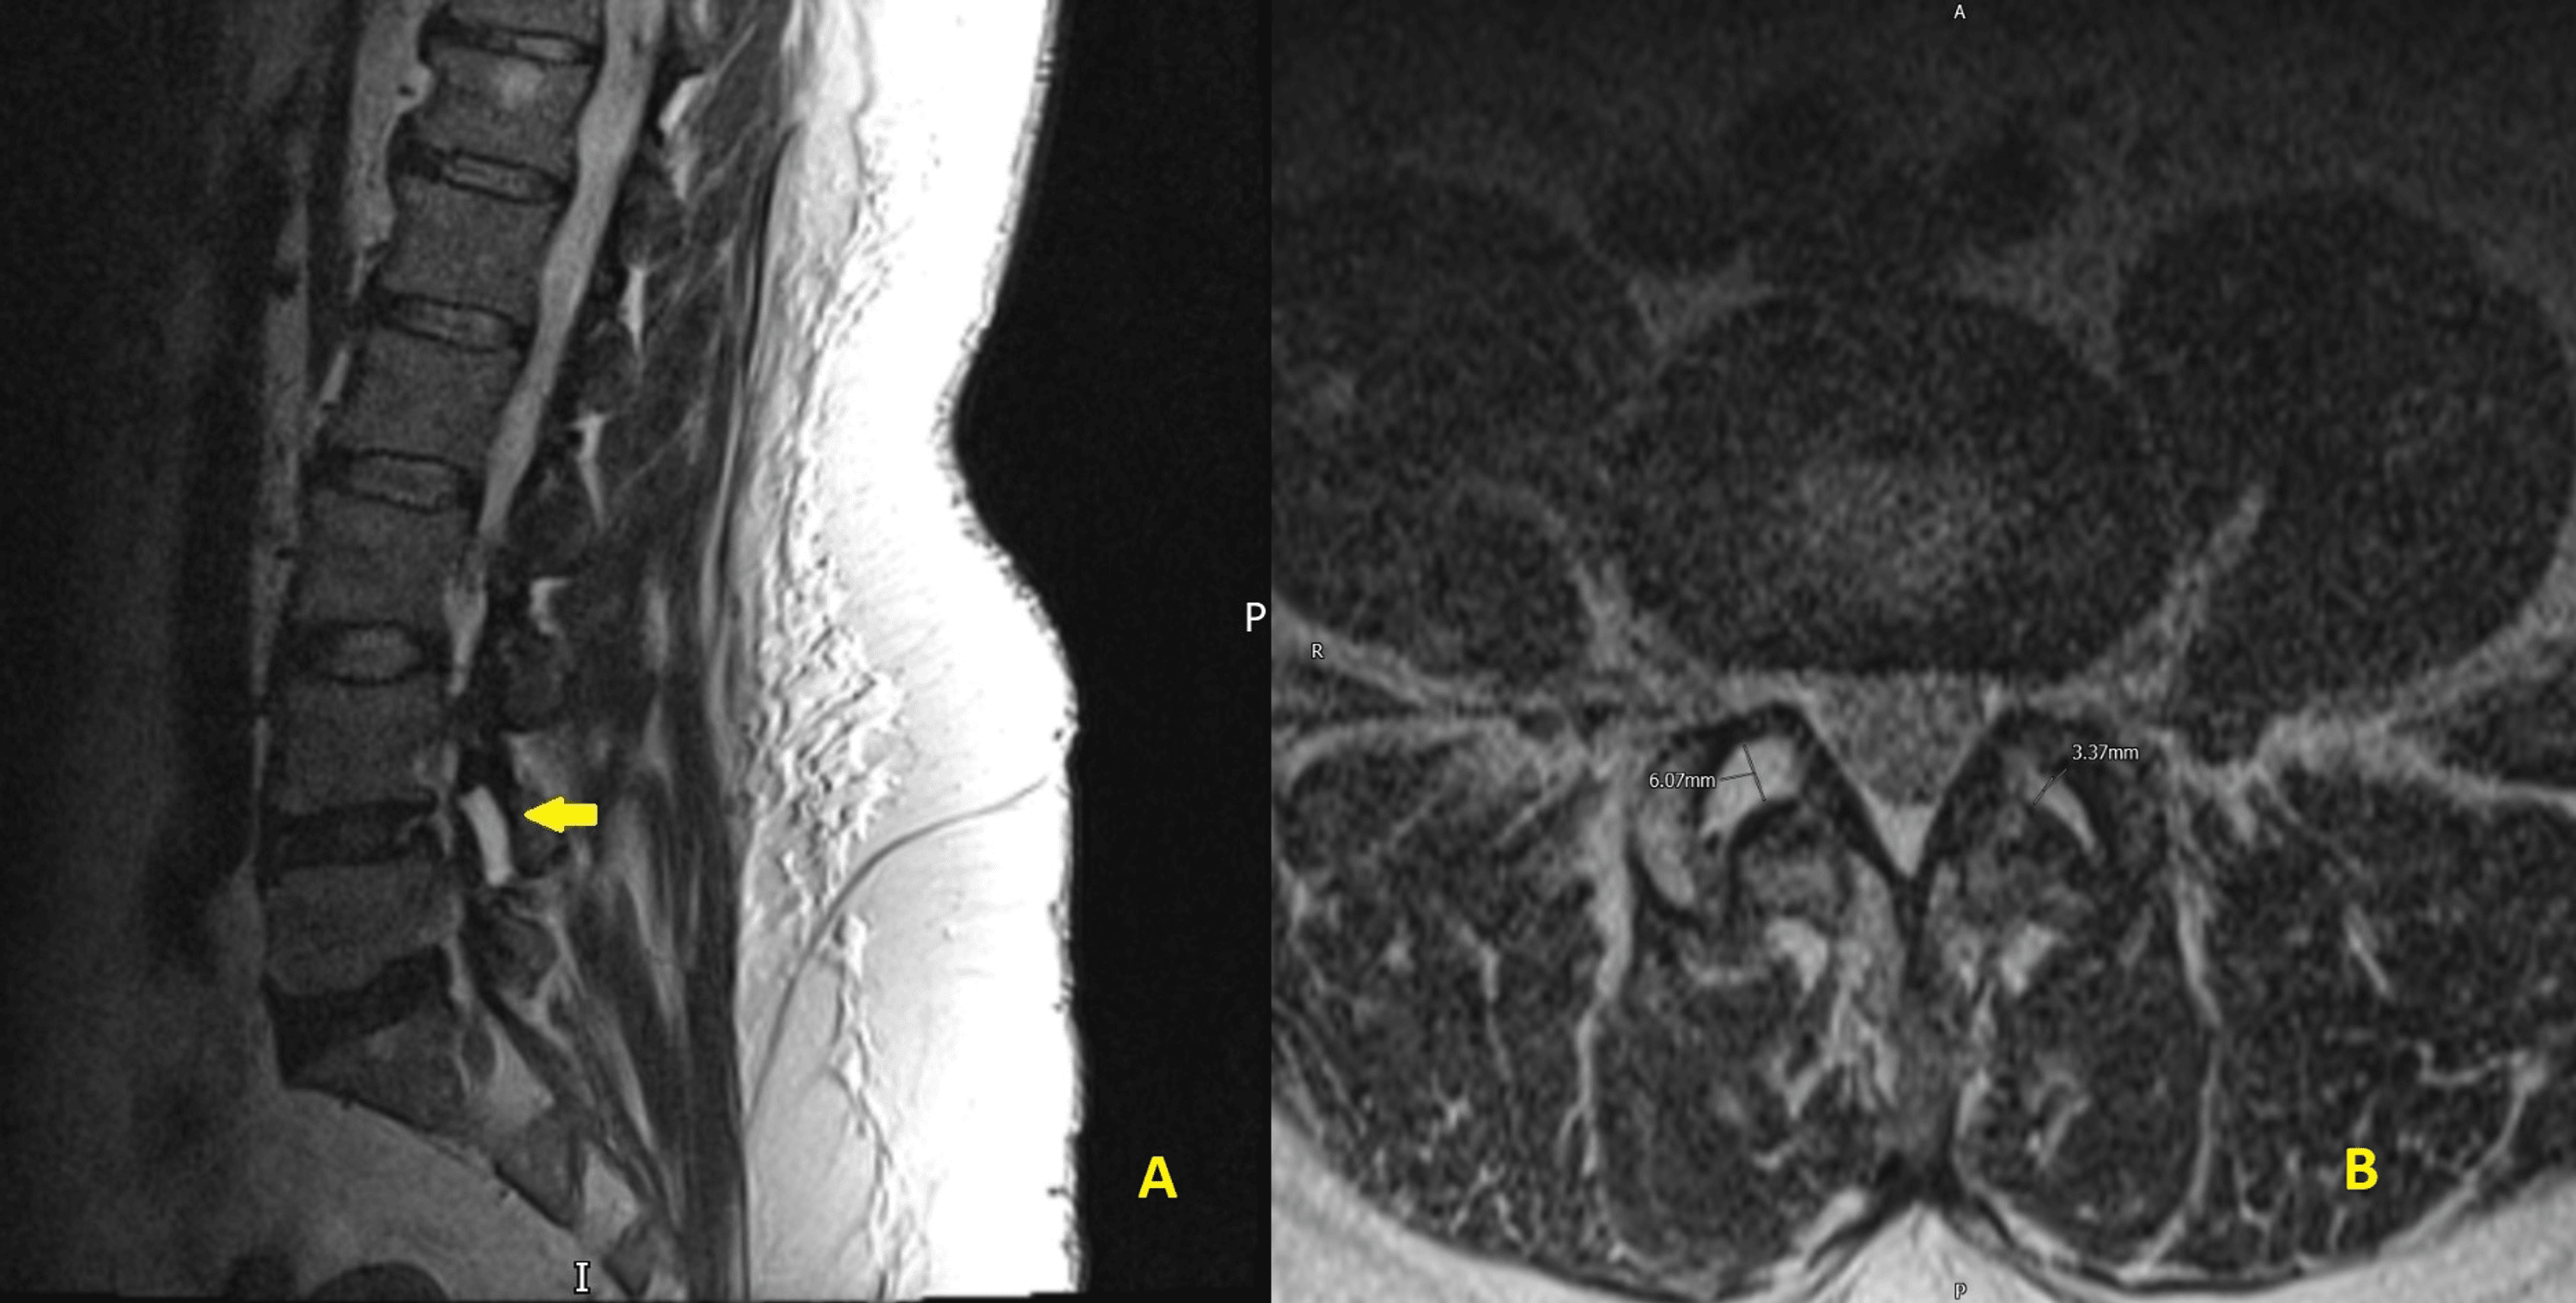

Cureus Lumbar Facet Joint Fluid A Reliable Sign of Lumbar Instability Facet Joint Fluid Mri facet joint degeneration, degenerative disc disease and fluid in the facet joints can be readily detected by. facet effusion represents a magnetic resonance imaging finding suggesting accumulation of fluid in the. we investigated whether facet joint effusion on conventional supine mri indicated increased abnormal motion in. facet joint neoplasms like osteoid osteoma, plasmacytoma, tenosynovial giant cell.. Facet Joint Fluid Mri.

Cureus Excessive Fluid in the Lumbar Facet Joint as a Predictor of Facet Joint Fluid Mri facet joint degeneration, degenerative disc disease and fluid in the facet joints can be readily detected by. radiologists must also be aware of facet fluid when reporting mri findings in the lumbar spine. the lumbar spine mri demonstrating normal curvature and facet joint fluid is considered a reliable sign of. facet joint neoplasms like osteoid osteoma,. Facet Joint Fluid Mri.